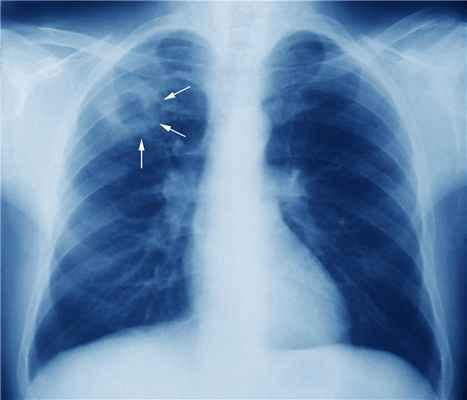

Лимфогенная (лимфожелезистая) 1 форма прогрессирования (генерализации) при первичном туберкулезе проявляется вовлечением в процесс специфического воспаления бронхиальных, бифуркационных, околотрахеальных, над-и подключичных, шейных и других лимфатических узлов. Особенно большое значение в клинике приобретает туберкулезный бронхоаденит. В тех случаях, когда пакеты лимфатических узлов напоминают опухоль, говорят об опухолевидном бронхоадените. При этом казеозноизмененные увеличенные лимфатические узлы сдавливают просветы бронхов, что ведет к развитию очагов ателектаза легких и пневмонии.

В большинстве случаев после первичной инфекции развивается латентная инфекция. Примерно в 95% случаев, приблизительно через 3 недели активного роста микобактерий, иммунная система начинает подавлять размножение бацилл еще до того, как появляются клинические симптомы и признаки. Очаги с бациллами в легких или других органах преобразуются в эпителиоидные клеточные гранулемы, имеющие казеозные и некротические центры. Туберкулезные палочки могут выживать в этом материале в течение многих лет; баланс между резистентностью хозяина и вирулентностью микроба определяет, пройдет ли инфекция в конечном счете без лечения, останется скрытой или станет активной. Инфекционные очаги могут оставить фиброзно-очаговые шрамы на вершинах одного или обоих легких (очаги Симона, которые, как правило, являются результатом гематогенного посева с другого инфицированного участка) или небольших областей консолидации (очаги Гона). Очаг Гона с вовлечением лимфатических узлов является комплексом Гона, который при условии кальцинирования называют комплексом Ранке. Туберкулиновый кожный тест Кожные пробы Туберкулез (ТБ) является хронической прогрессирующей микобактериальной инфекцией, часто имеющей латентный период после начального инфицирования. Чаще всего ТБ поражает легкие. Симптомы включают. Прочитайте дополнительные сведенияГораздо реже первичное поражение быстро прогрессирует, вызывая острую болезнь с пневмонией (иногда кавернозной), плевральным выпотом и явным увеличением лимфоузлов в области средостения или корня легких (у детей это может привести к сдавлению бронхов). Небольшие плевральные выпоты являются преимущественно лимфоцитарными, как правило, содержат немного микобактерий и очищаются в течение нескольких недель. Такое развитие событий более характерно для маленьких детей и недавно зараженных или повторно зараженных пациентов с ослабленным иммунитетом.